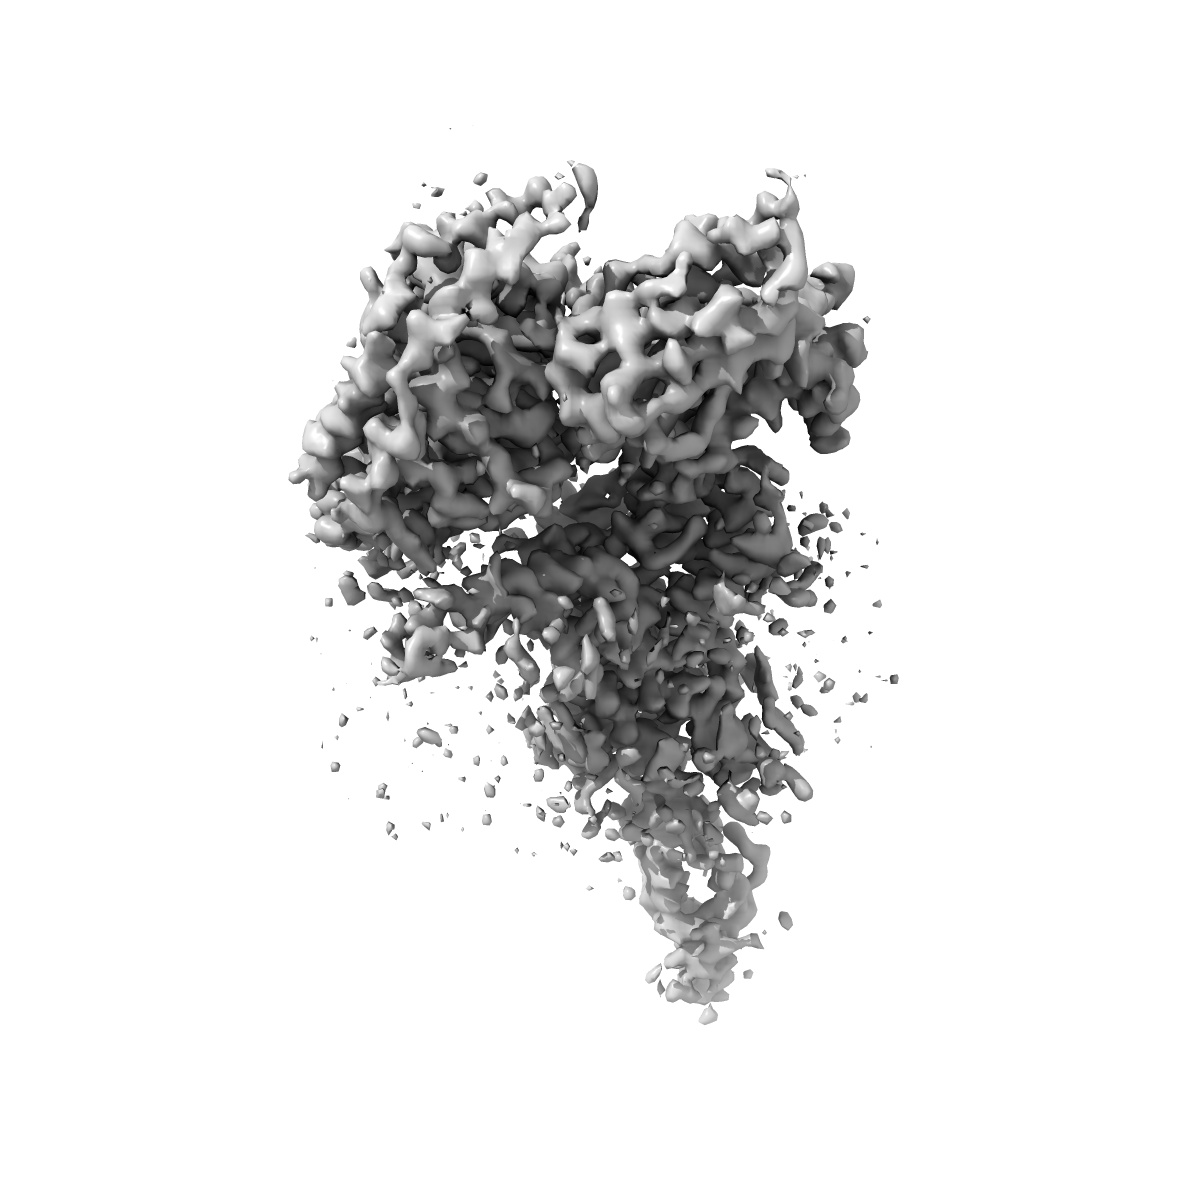

EMD-0411

Cryo-EM structure of parathyroid hormone receptor type 1 in complex with a long-acting parathyroid hormone analog and G protein

Single-particle3.5 Å

Sample: Cryo-EM structure of parathyroid hormone receptor type 1 in complex with a long-acting parathyroid hormone analog and G protein

Structure and dynamics of the active human parathyroid hormone receptor-1.

(2019) Science , 364 , 148 - 153